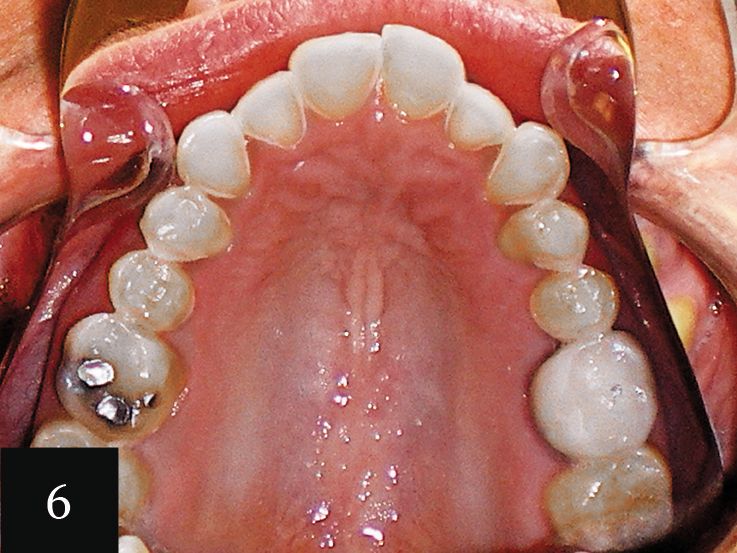

Case No. 2

This case showcases a woman in her mid-30s who had an anterior open bite, as well as a history of bulimia (Figs. 5-6). The eating disorder led to severe wear, which can be seen on the upper arch. The gum line was also very irregular. The impression accurately captured the detail of the teeth and a series of 12 aligners was made.

Following this initial phase, an additional impression was taken for six more aligners. Finally, one more impression was taken with Imprint 3 VPS impression material to create crowns for tooth Nos. 3-14. This treatment significantly elevated the patient’s level of confidence in her smile (Figs. 7 and 8).